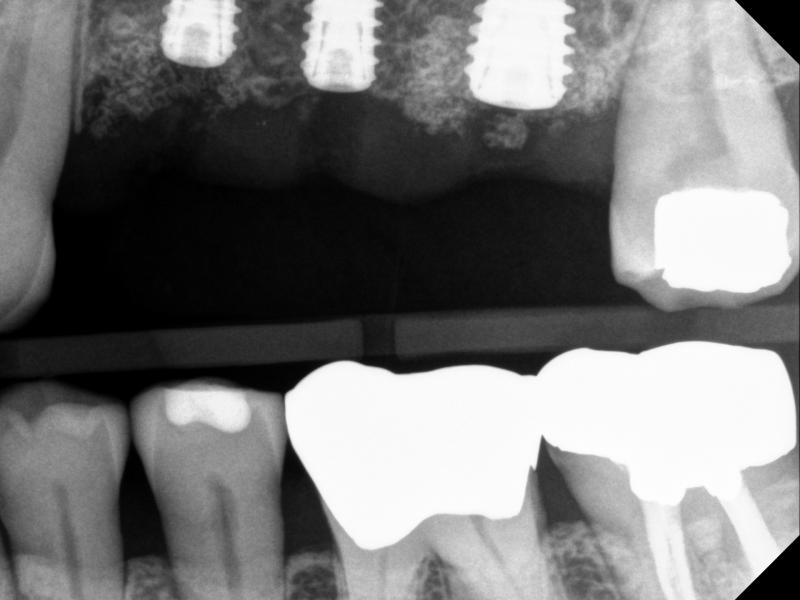

Multiple Implants

The following is an example of a multi-implant case, in which there is no room for error. Thus, a fully-guided system must be used for implant placement (Figs.7 & 8)

(a)

(b)

Fig. 8. A multi-implant case, using fully guided sytem, Sites #12, #13, and #14 -- implants and cover screws: (a) PA, and (b) BW

Note that for Site #14, the implant was tilted a bit to the mesial side (compared to the planning).